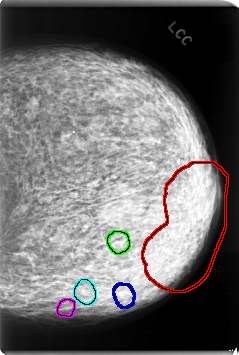

C_0078_1.LEFT_CC

FILE: C_0078_1.LEFT_CC.OVERLAY

TOTAL_ABNORMALITIES 5

ABNORMALITY 1

LESION_TYPE CALCIFICATION TYPE PLEOMORPHIC DISTRIBUTION CLUSTERED

ASSESSMENT 5

SUBTLETY 5

PATHOLOGY MALIGNANT

TOTAL_OUTLINES 1

BOUNDARY

ABNORMALITY 2

ABNORMALITY 3

ABNORMALITY 4

ABNORMALITY 5